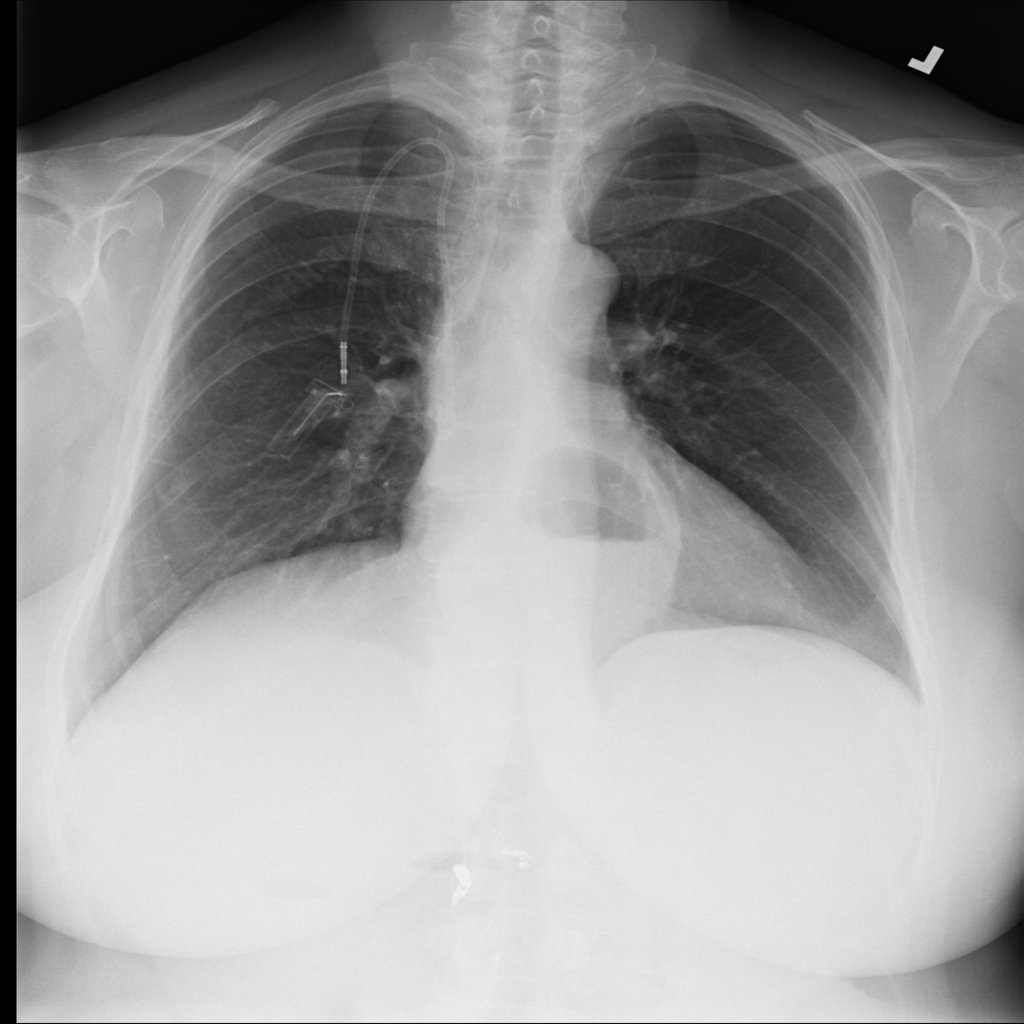

PAT-C048 · IMG-000Hernia

PAT-C048 · IMG-000

PA